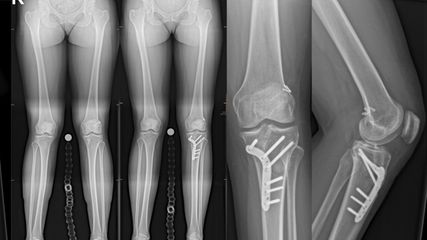

In einer finnischen Studie zeigten Tammelin et al., dass 93% der Verletzungen durch den 1st und 2nd Survey detektiert wurden, weitere knapp 4% durch den 3rd Survey, weitere 2,6% danach noch während des stationären Aufenthalts und 0,1% erst nach der Entlassung.4 Die MIR nach dem 1st–3rd Survey lag demnach noch immer bei 2,6%. In dieser Arbeit zeigte sich aber, dass muskuloskelettale Verletzungen am häufigsten übersehen bzw. nachdetektiert wurden (Abb. 2).

Zwei Analysen aus dem deutschen Traumaregister von Fitschen-Oestern und Kollegen betreffend MI der Extremitäten zeigten eine MIR von 6,6% bei Hand-/Unterarmverletzungen respektive von 6,5% bei Fußverletzungen.8,9 Erhöhte OR bei „missed foot injuries“ wurden errechnet für einen suizidalen Unfallmechanismus (OR 2,7), gleichzeitige Tibiafrakturen (OR 2,5) und Fibulafrakturen (OR 2,6). Hingegen konnte kein Zusammenhang mit dem GCS und MI im Fußbereich gefunden werden. Immerhin mussten 56% der verspätet diagnostizierten Fußverletzungen operativ versorgt werden (kein wesentlicher Unterschied in der operativen Indikationsrate zu den frühzeitig diagnostizierten Verletzungen). Auch in dieser Auswertung gab es die meisten Fußverletzungen bei Verkehrsunfällen mit Patienten als Insassen. Hinsichtlich der Hand-/Unterarmverletzungen waren die am häufigsten übersehenen Verletzungen Nervenverletzungen (25%), gefolgt von Sehnenverletzungen (11%) und karpalen Verletzungen (11% Frakturen und Luxationen). Die höchste primäre Detektionsrate lag bei Ellbogenverletzungen, Radius- und Ulnafrakturen sowie Gefäßverletzungen. Auch bei dieser Studie konnte kein Zusammenhang mit dem GCS gefunden werden, wobei nur 15% der Patienten mit Unterarm-/Handverletzungen einen GCS <8 hatten. Ein Bias bei den Daten aus dem Traumaregister entsteht auch hinsichtlich des GCS-Erhebungszeitpunktes. Der GCS wird regelhaft bei der Aufnahme erfasst; wie hoch er beim 2nd oder 3rd Survey war, war nicht erhebbar.